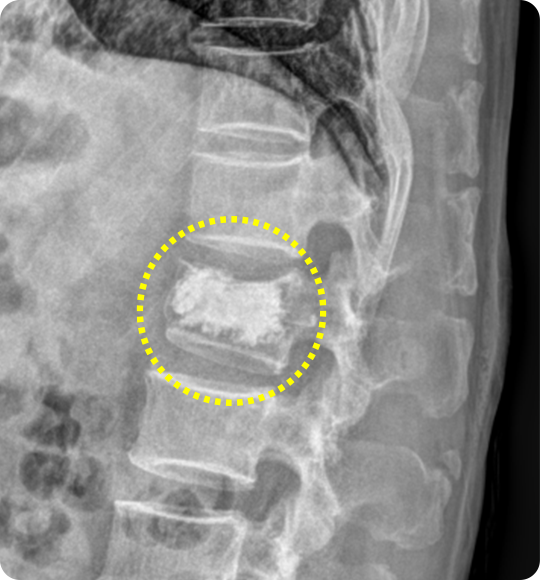

척추체 성형술 전

척추체 성형술

이때 골절로 약해진 척추체 내부에 특수 의료용 시멘트를 주입해 척추를 단단히

보강하고 통증을 완화하는 치료가 바로 척추체 성형술입니다.